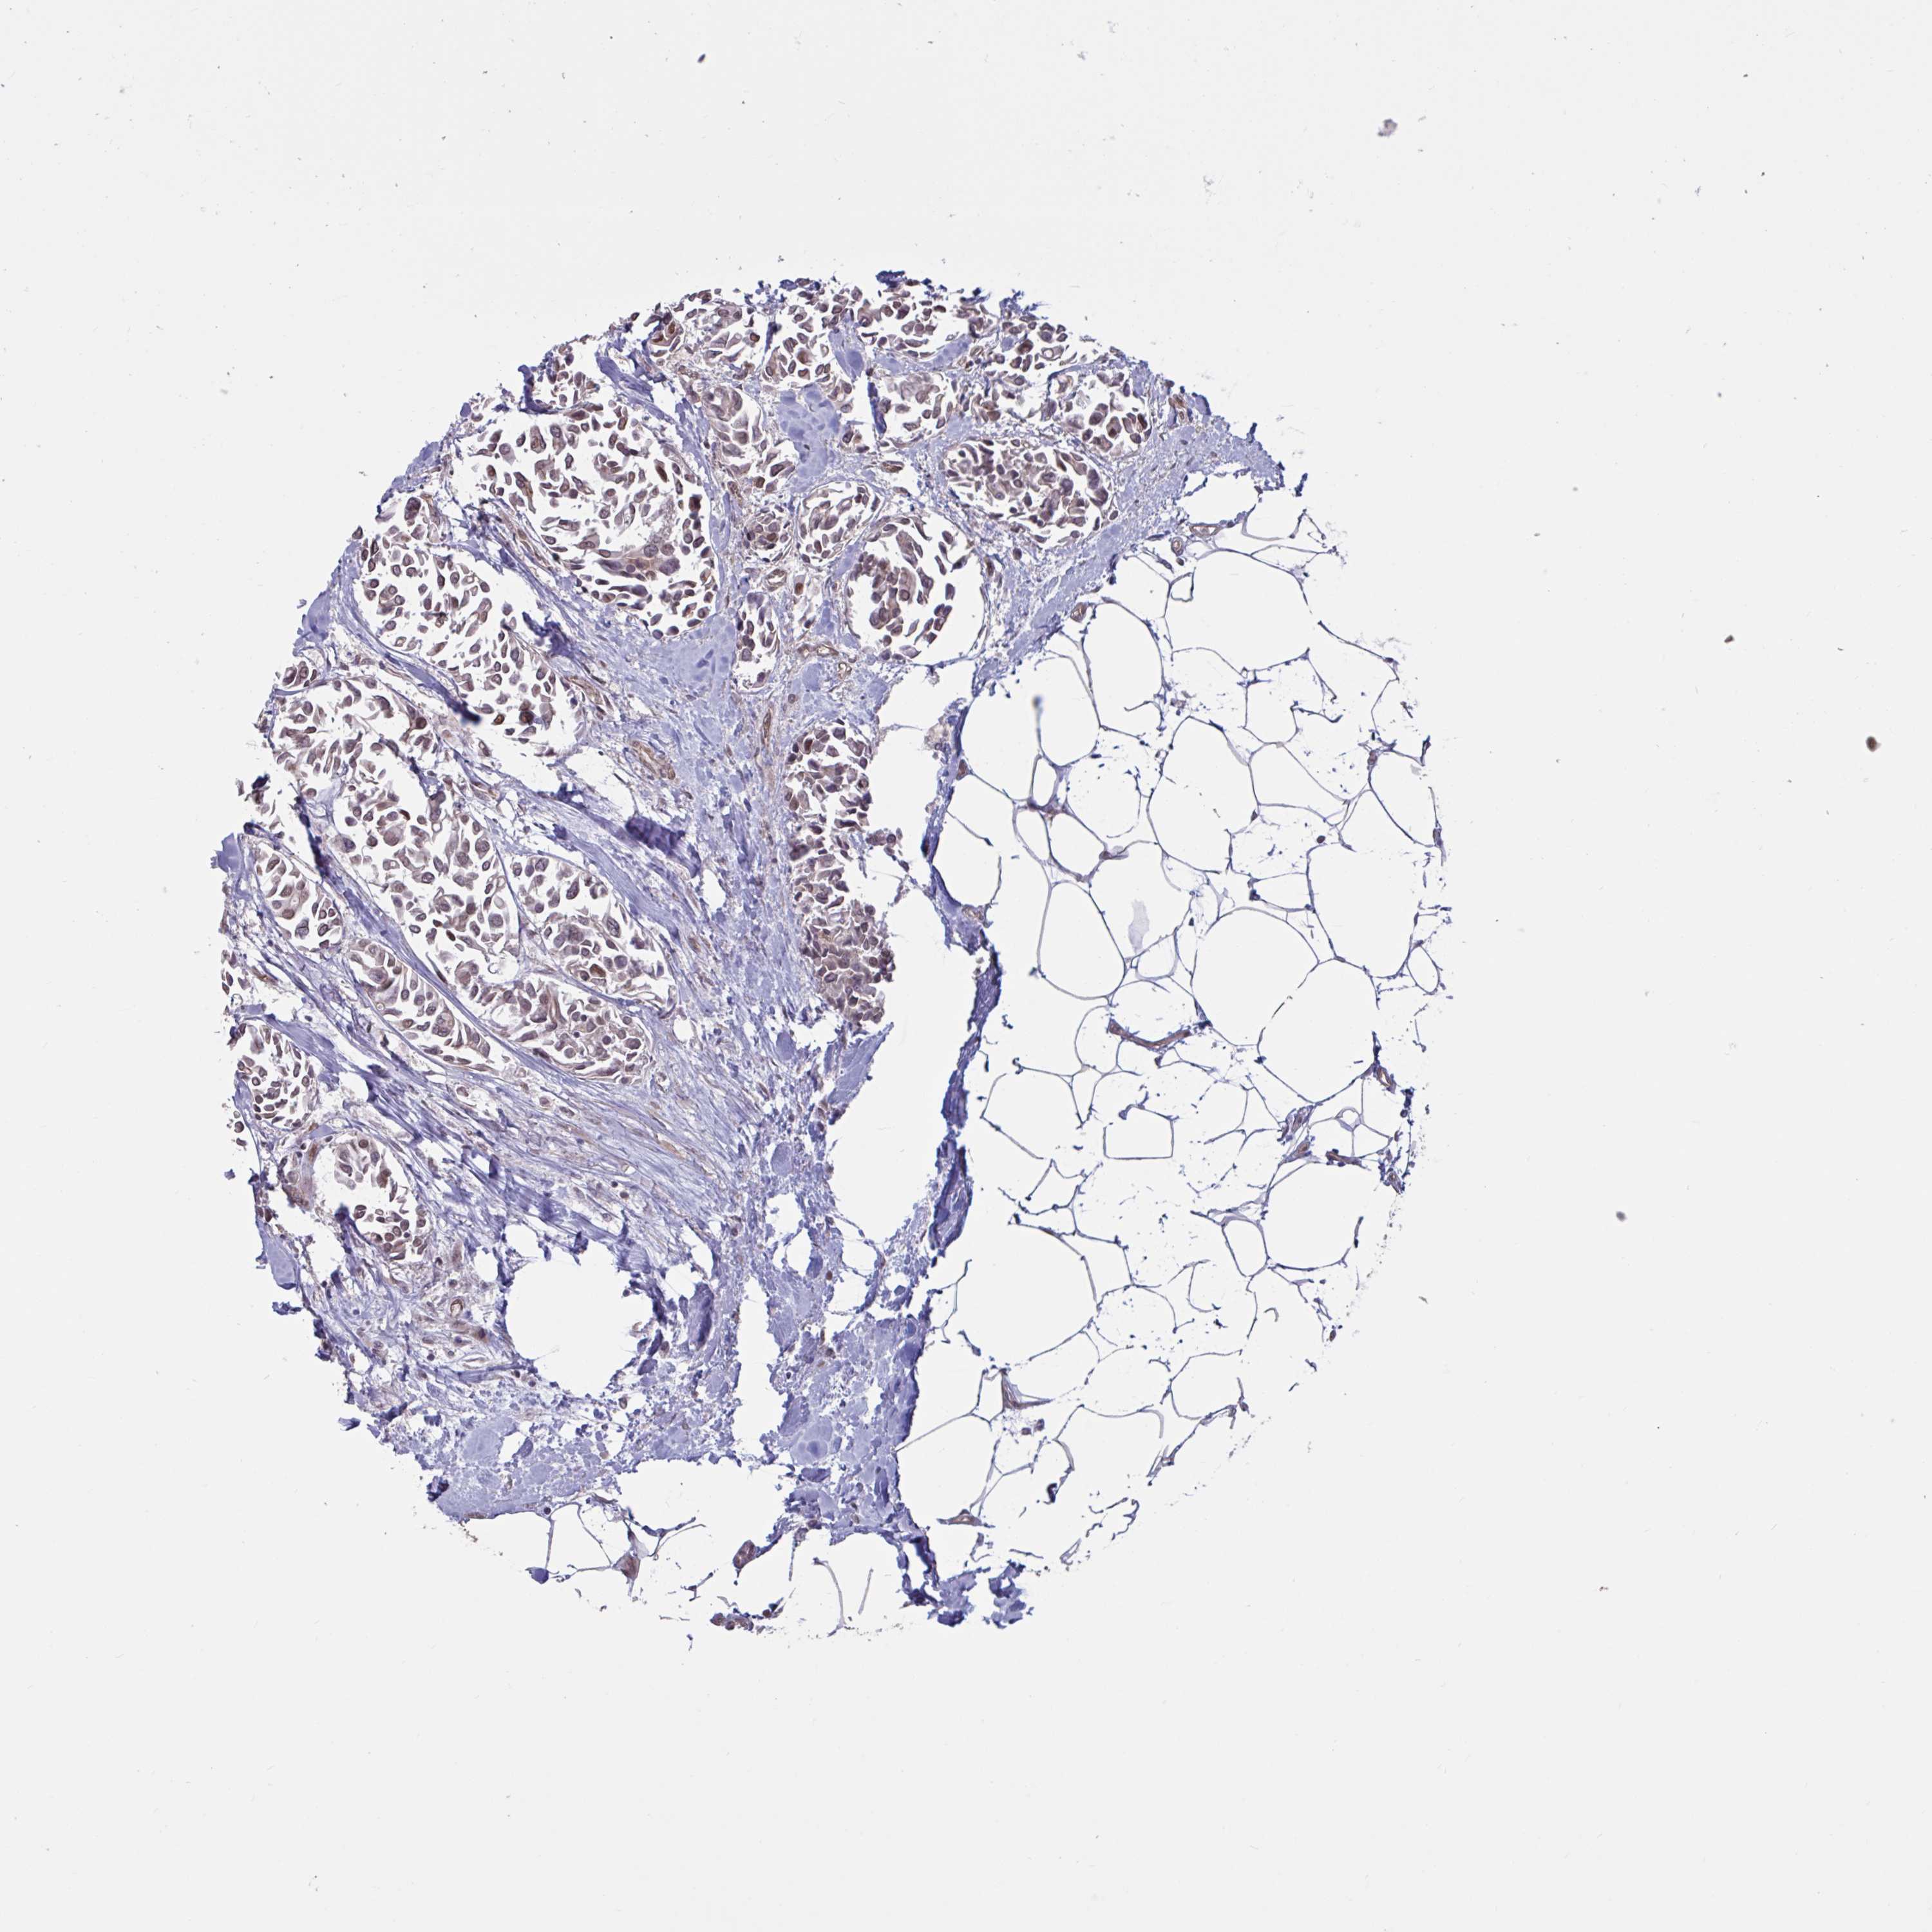

BRCA TCGA BRCA VALIDATION PROTEIN EXPRESSION